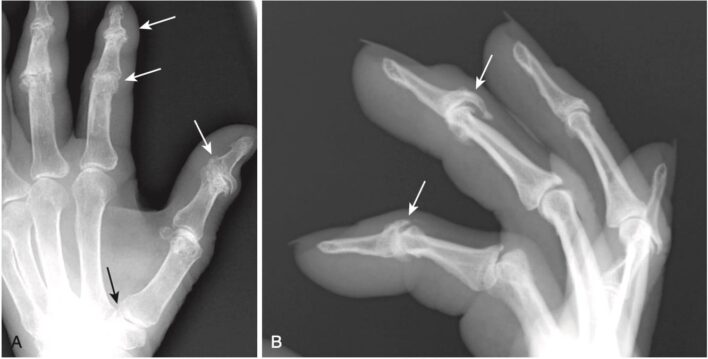

Hình 6. Thoái hóa khớp bàn tay. A và B, Ở bàn tay, thoái hóa khớp chủ yếu ảnh hưởng đến các khớp liên ngón xa (DIP) và sau đó là liên ngón gần (PIP). Có các gai xương ở DIP và PIP (mũi tên trắng), và các khe khớp bị hẹp (cả A và B). Ngoài ra còn có đặc xương dưới sụn hiện diện ở khớp cổ – bàn (CMC) của ngón cái (mũi tên đen). Thoái hóa khớp bàn tay thường xảy ra ở phụ nữ lớn tuổi.

- Các ăn mòn thường nằm ở giữa trong khớp và kết hợp với các gai xương nhỏ, có thể tạo nên dấu hiệu gọi là biến dạng cánh mòng biển (gull-wing deformity) (Hình 8).

Hình 8. Thoái hóa khớp ăn mòn. Các dấu ăn mòn thường nằm ở trung tâm trong khớp (mũi tên đen) và kết hợp với các gai xương nhỏ (mũi tên trắng), tạo nên biến dạng cánh mòng biển.